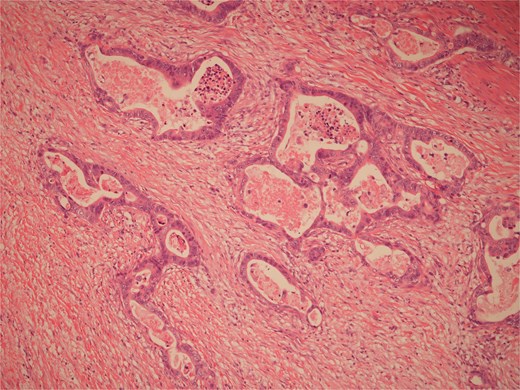

Histopathological examination of surgical specimens revealed three distinct neoplasms: (i) invasive colonic adenocarcinoma (Figs 4 and 5), (ii) jejunal NET (Figs 6 and 7), and (iii) small-lymphocytic lymphoma (Figs 8 and 9). Morphological assessment supported by immunohistochemical profiling confirmed each represented an independent primary, with no evidence of a shared clonal origin. The findings were subsequently reviewed at the Multidisciplinary Meeting alongside Oncology and Haematology specialists, and adjuvant single-agent chemotherapy was initiated, with planned surveillance of the indolent lymphoma.

High power view of well-differentiated neuroendocrine tumour showing nests of monotonous cells with round nuclei and “salt and pepper” chromatin.